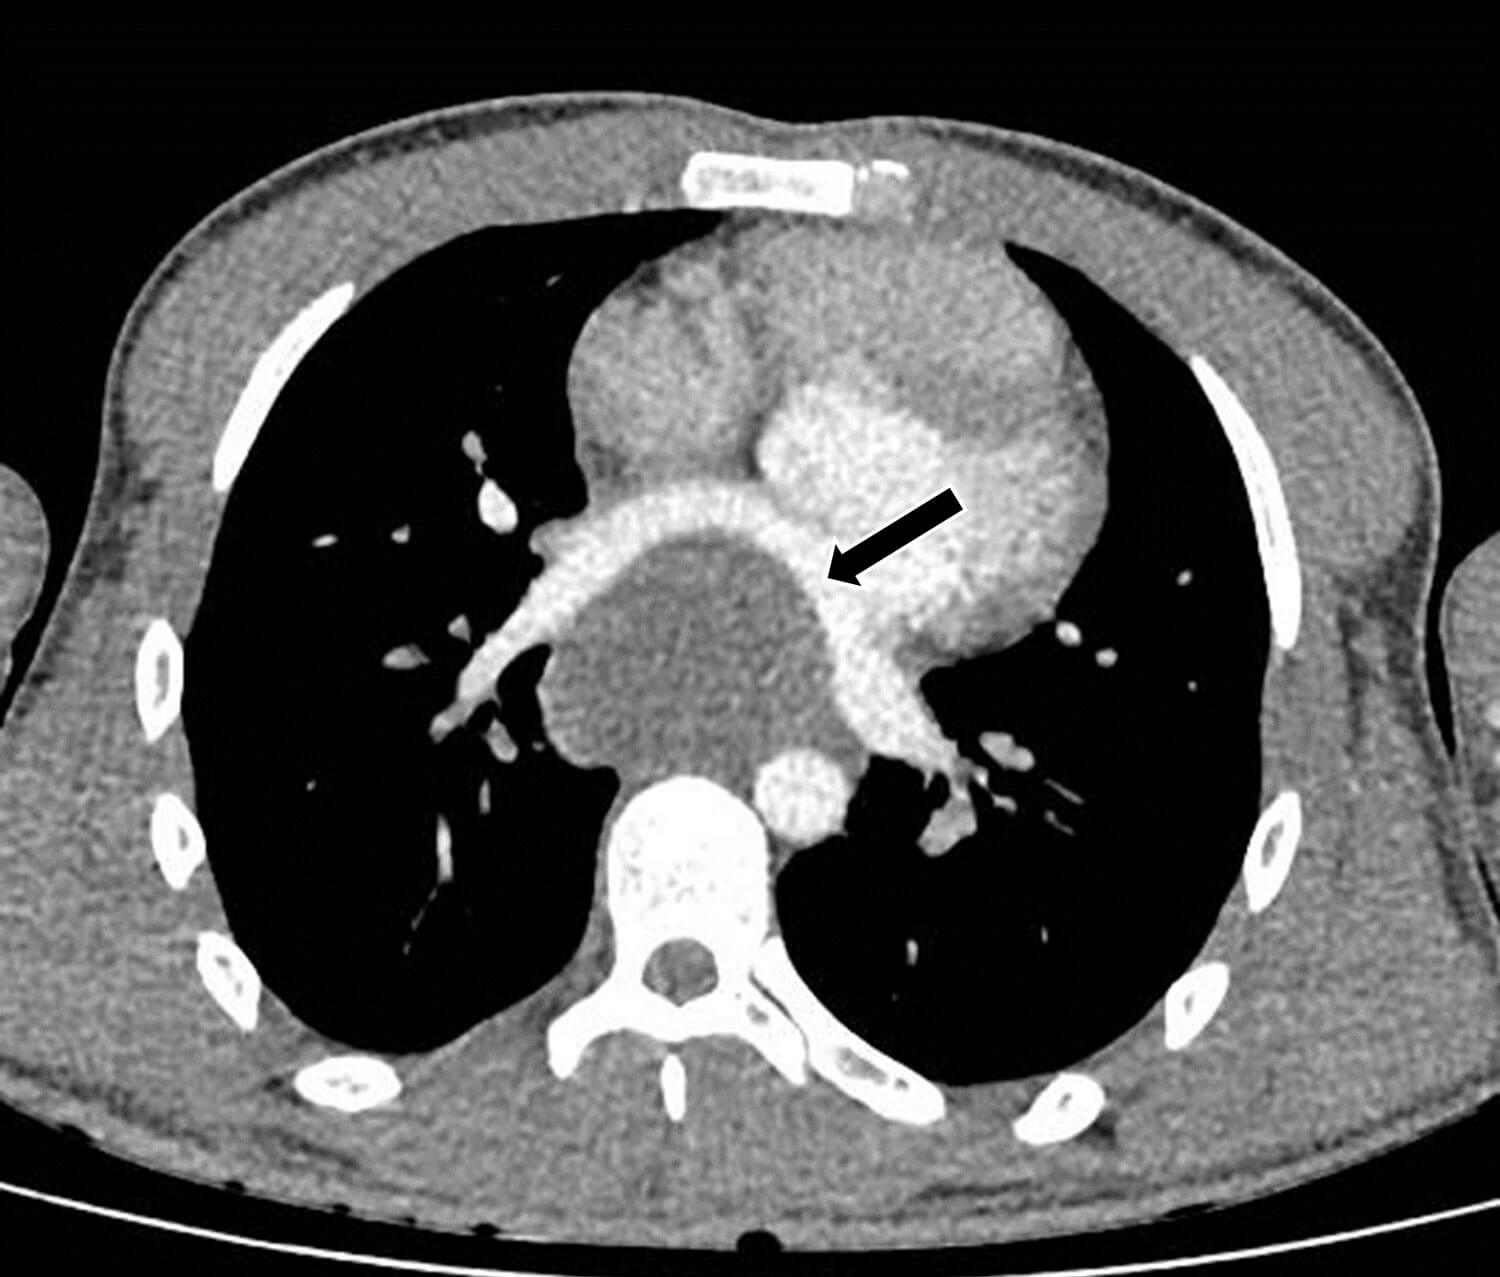

A 23-year-old man presented to A&E with sudden onset chest pain, hypotension and tachycardia. A chest x-ray was suggestive of a mass posterior to the heart, and a bedside echocardiogram was suspicious for an atrial mass measuring 6 x 6cm. The patient was reviewed by both the cardiology and respiratory teams. A CT and MRI thorax showed a large mediastinal mass compressing the left atrium, but the aetiology was inconclusive with differentials including a benign bronchogenic cyst (Figure 4). Imaging surveillance was recommended and the patient was discharged home.

Figure 4: 7 x 5 x 7cm low attenuation mediastinal mass compressing the left atrium.